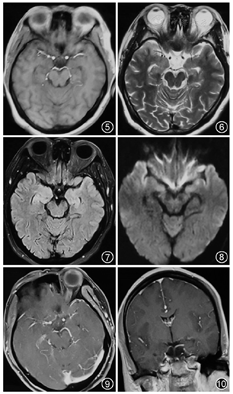

患者45岁,女性,既往体健。因"记忆力减退、精神异常3个月"余于2018年5月25日入滨州医学院附属学院。患者于2018年2月14日无明显诱因出现记忆力减退,表现为近期事件遗忘,反应尚可,可正常交流,2月16日后出现情绪不稳定,烦躁不安,时有喊叫及自言自语,交流困难,睡眠障碍,当时测体温38 ℃,遂就诊博兴县人民医院,颅脑MRI提示双侧海马硬化(图1,图2,图3,图4),血常规:嗜酸细胞百分比0%,单核细胞计数0.73×109/L,嗜酸细胞计数0×109/L,余未见明显异常。未予治疗,由于上述症状持续存在,于2月18日就诊胜利油田中心医院,行颅脑MRI+磁共振波谱(MRS)示双侧海马FLAIR信号增高,不除外海马硬化;MRS示左侧海马N-乙酰天冬氨酸(NAA)减低,NAA/肌酐、NAA/肌酐+胆碱比值降低。腰椎穿刺:颅内压190 mmH2O(1 mmH2O=0.009 8 kPa),脑脊液常规:无色透明,无凝块,潘氏蛋白定性(-),白细胞计数3×106/L,白细胞单核100%。脑脊液生化:蛋白0.41 g/L,葡萄糖3.8 mmol/L,氯化物122.3 mmol/L,腺苷脱氨酸0.3 U/L。新型隐球菌涂片、抗酸杆菌涂片阴性。脑脊液神经系统副肿瘤综合征系列:阴性。脑脊液自身免疫性脑炎系列:N-甲基-D-天冬氨酸受体(NMDA)型抗体、α-氨基-3-羟基-5-甲基-4-异恶唑丙酸(AMPA)1型抗体、AMPA2型抗体、抗富亮氨酸胶质瘤失活蛋白抗体、抗接触蛋白关联蛋白2(CASPR2)、抗GABAB受体抗体IgG阴性。血清自身免疫性脑炎系列:NMDA型抗体、AMPA1型抗体、AMPA2型抗体、抗富亮氨酸胶质瘤失活蛋白抗体、抗CASPR2、抗GABAB受体抗体IgG阴性。血清肿瘤标志物:鳞状细胞癌相关抗原、胃泌素释放肽前体、糖链抗原、神经元特异性烯醇化酶、细胞角蛋白19片段、甲胎蛋白、癌胚抗原、异常凝血酶原在正常范围,糖链抗原72-4 16.24 U/ml(高于正常值)。血常规:嗜酸细胞百分比0.3%,单核细胞计数0.64×109/L,余未见明显异常。诊断:病毒性脑炎、双侧海马硬化。给予阿昔洛韦、奥拉西坦治疗15 d出院,出院时无发热,情绪较稳定,仍近记忆力减退。5月15日受惊吓(打雷)后再次出现烦躁不安、时有吵闹,胡言乱语,无法交流,夜间不眠,测体温38.6 ℃,再次就诊博兴县人民医院,行颅脑CT未见异常,血常规示中性粒细胞百分比75.6%,淋巴细胞百分比19.1%,嗜酸性粒细胞百分比0.3%,余无异常,未予治疗。后再次就诊胜利油田中心医院,颅脑MRI+增强示双侧颞叶海马区斑片状长T2高信号,弥散加权成像(DWI)异常信号;增强后未见异常强化,除外脑炎可能(图5,图6,图7,图8,图9,图10)。胸部CT示右肺下叶占位,建议增强扫描,双肺间质性改变(图11,图12)。血常规:单核细胞百分比13.7%,余无异常。肿瘤标志物:鳞状细胞癌相关抗原8.60 ng/ml,神经元特异性烯醇化酶48.13 ng/ml。血T细胞绝对值计数:CD3+细胞绝对计数1 600×109/L,CD4+772×109/L,CD8+724×109/L,CD4+/CD8+:1.07,均在正常范围。诊断:右肺癌、颅内感染?认知障碍,给予阿昔洛韦、头孢曲松、吡拉西坦、丙戊酸、苯巴比妥钠等治疗7 d,体温波动在37.2~38.1 ℃,症状无好转,为求进一步诊治于5月25日入滨州医学院附属医院。入院体格检查:体温37.5 ℃,意识清楚,反应迟钝,交流困难,言语欠流利,记忆力、计算力、定向力减退,余神经系统体格检查无明显异常。相关检查回报:血清副肿瘤综合征检测:抗Hu、Yo抗体(+)。氟代脱氧葡萄糖(FDG)-正电子发射计算机断层扫描(PET)示右肺高代谢肿块,纵隔内高代谢淋巴结,考虑右肺癌并淋巴结转移;直肠近肛管处FDG代谢增高;甲状腺双侧叶病变,代谢不高;双侧基底节区FDG代谢略稀疏。右肺占位穿刺活体组织检查:小细胞癌,免疫组织化学染色:细胞角蛋白(CK)(+)、突触素(+)、嗜铬素A(+)、CD56+、甲状腺转录因子-1(+)、Ki-67阳性率约90%(图13,图14,图15,图16)。脑电图示背景为弥漫性低-中波幅不规则慢波,两侧无明显不对称,基线不稳(图17)。